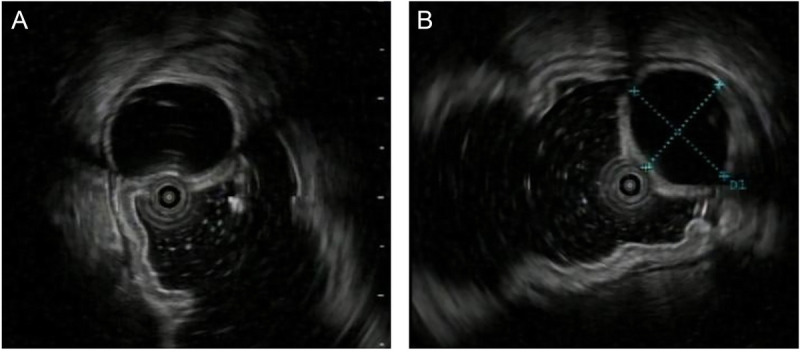

Intraductal papillary mucinous neoplasm originating from a heterotopic pancreas within the stomach.

起源于胃内异位胰腺的导管内乳头状粘液瘤。